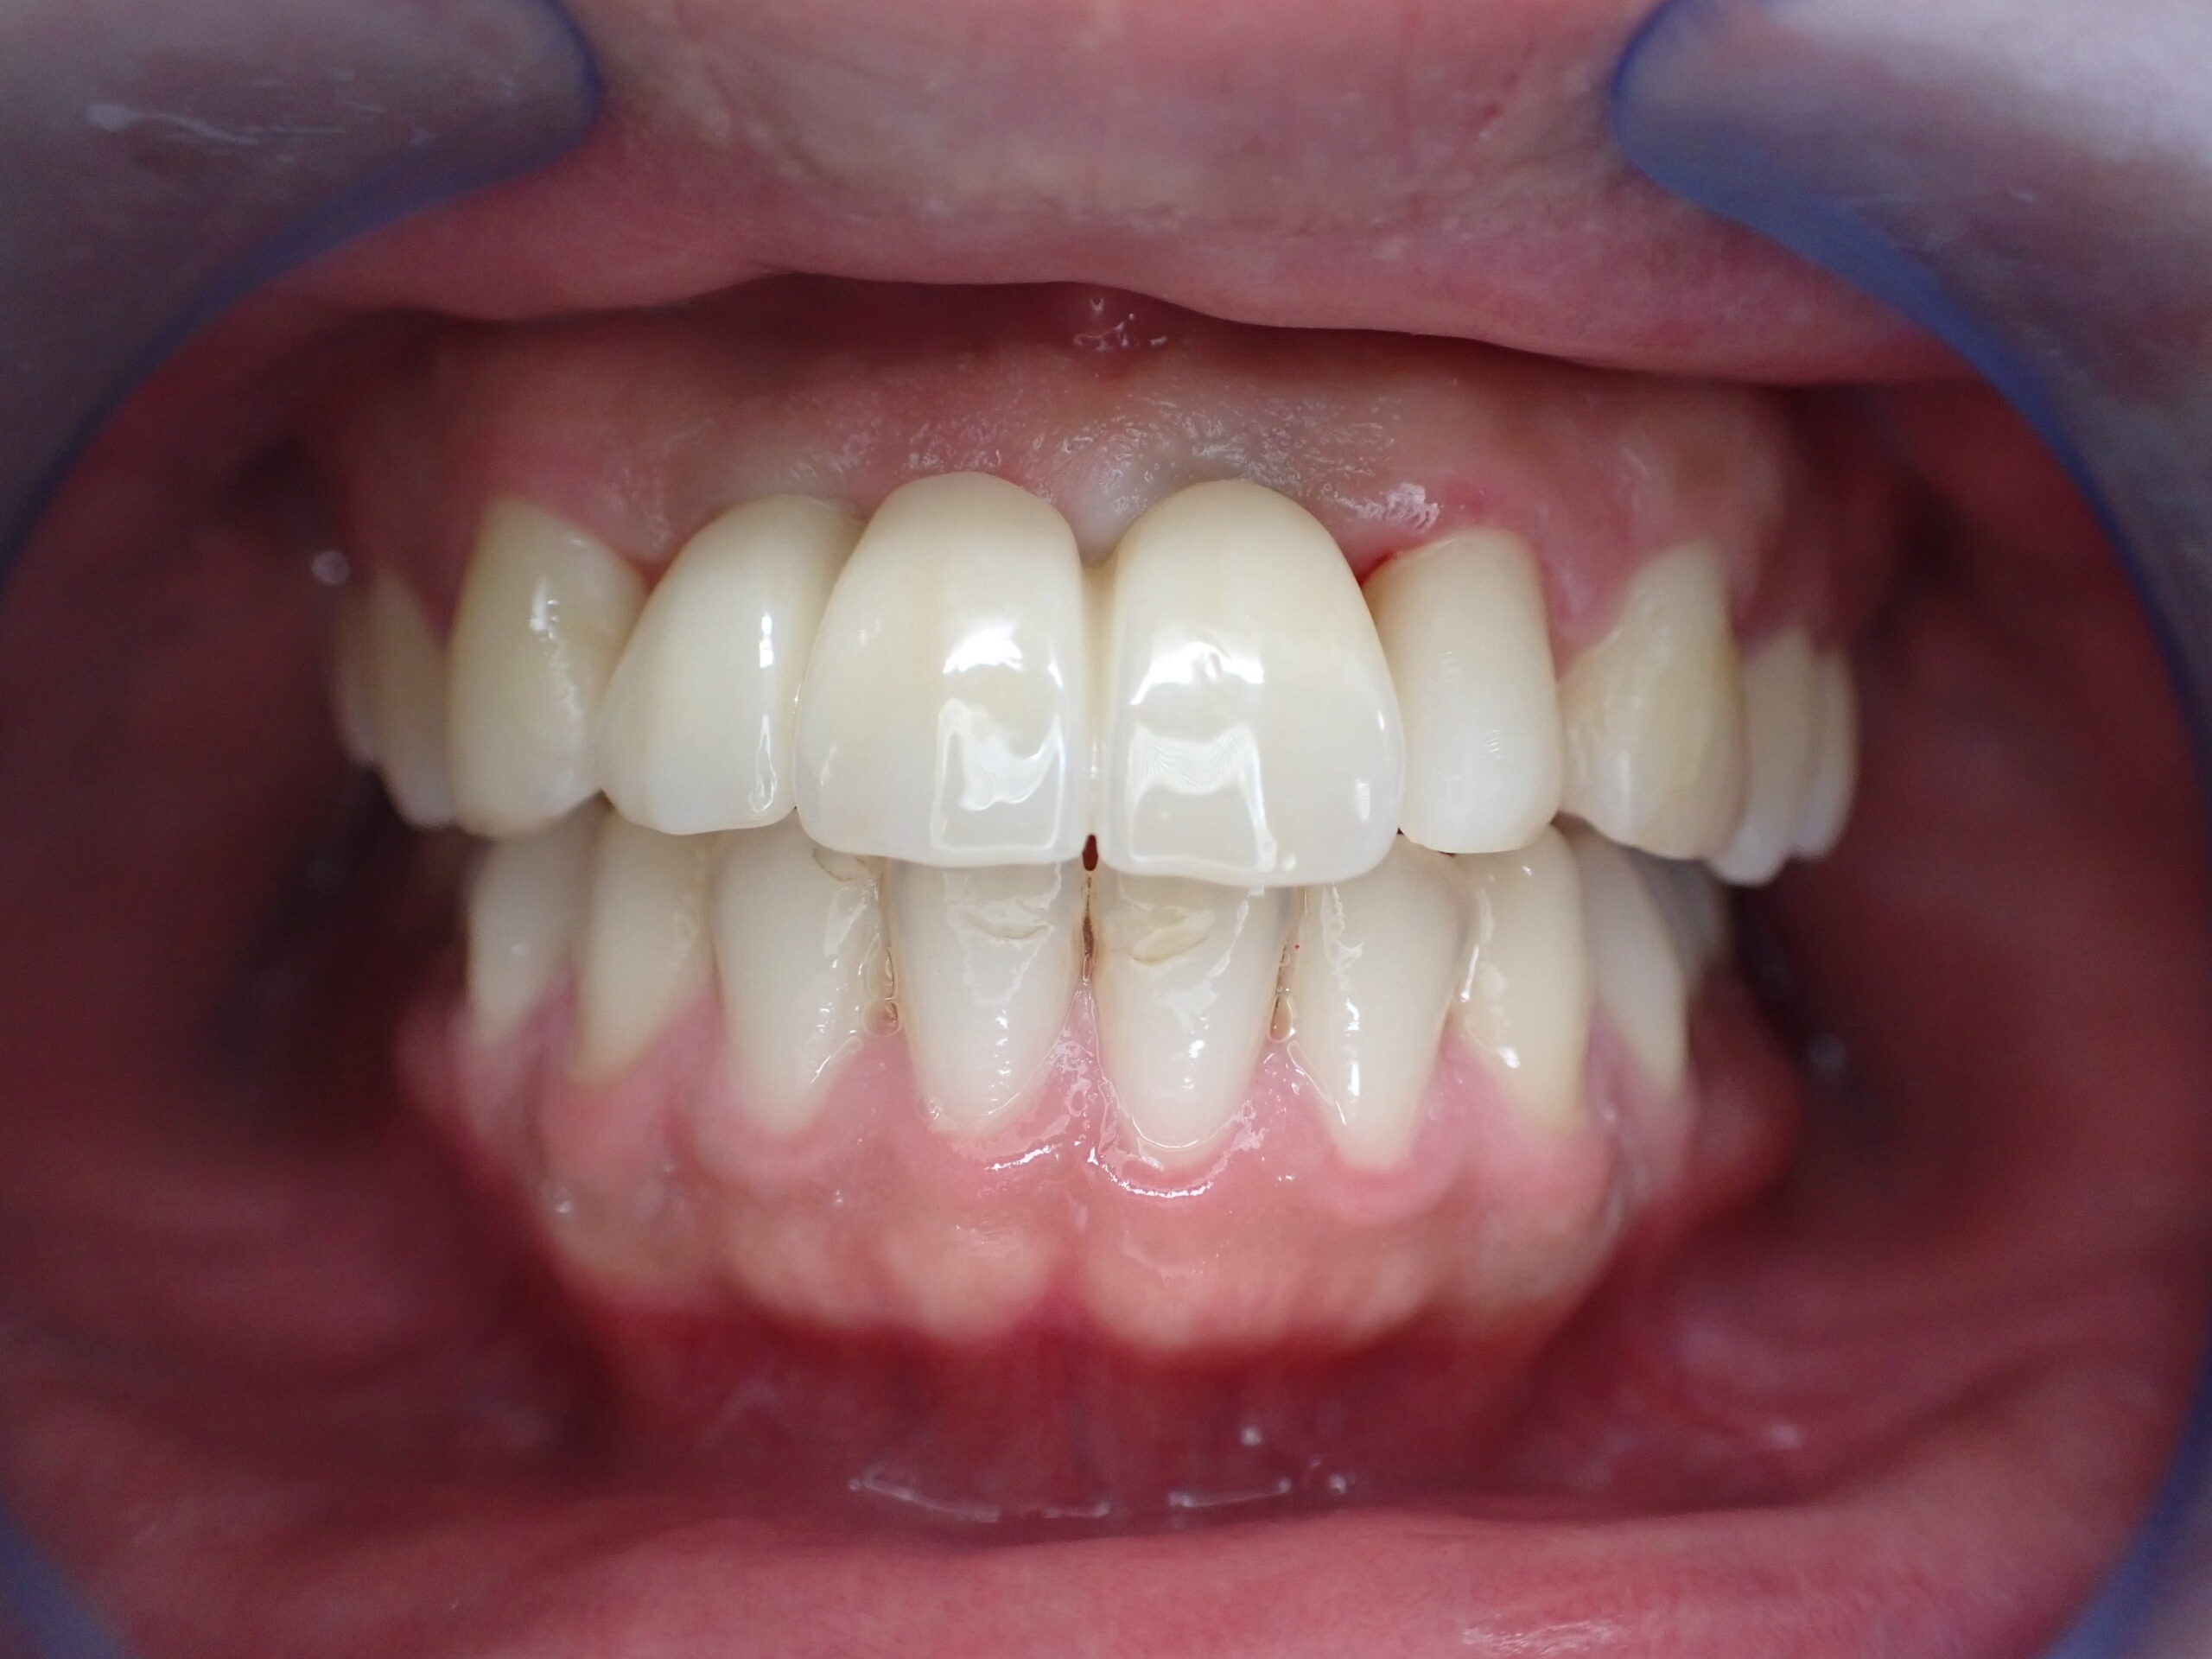

前歯インプラント症例

ブリッジではもう直せない症例です。インプラントで修復しました。